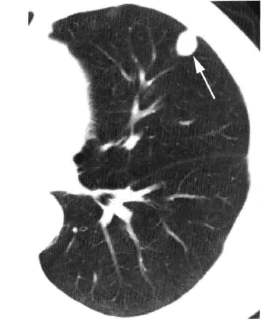

小J今年38岁,都市白领,6年前发现子宫平滑肌瘤,开始并不在意,当发现腹部明显增大,去做手术的时候却被告知可能是子宫肉瘤,经历了手术、化疗的一些列折腾,刚开始效果还是不错的,但是就在1年前的一次复查,她发现了肺转移、骨转移。现在每个月都要来医院接受化疗和预防骨折的药物治疗。但是,最近3次化疗后复查,肿瘤没有任何改善,新上的化疗方案似乎对她的肿瘤毫无作用。虽然化疗的副反应让她并不好受,但她依然坚持上班,一方面是为了生存,另一方面也能分散一部分注意力。然而这次复查的结果让她很不淡定,于是她找教授核实情况,希望能找到更好的解决方案。然而,她最终只是从教授脸上找回一脸的无奈!